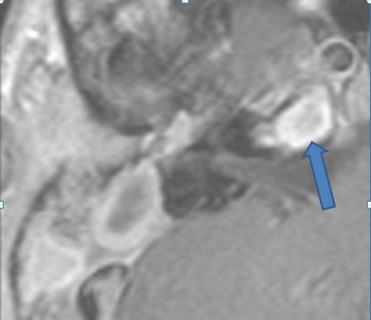

Acute and Subacute Bacterial Otomastoiditis

4. Acute coalescent or otherwise complex otomastoiditis with local complications (indicate specific complications).

5. Acute coalescent or otherwise complex otomastoiditis with intracranial complications (indicate specific complications).